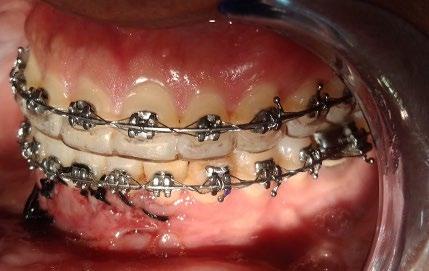

El tratamiento se realizó en las siguientes fases: la fase prequirúrgica incluyó la alineación, nivelación y la

extracción de los segundos premolares superiores e inferiores, con cierre de espacios. En la fase quirúrgica, se realizó una mentoplastia de avance e implantes en la zona malar. La fase postquirúrgica consistió en el detallado-retención. La aparatología utilizada fueron brackets de prescripción Roth .022 × .028; se colocaron bandas en los primeros molares superiores e inferiores, con tubos punteables en los O.D. 16, 26, 36 y 46, y tubos bondeables en el O.D. 27, además de un arco transpalatino y un arco lingual.

El tratamiento se realizó en las siguientes fases: la fase prequirúrgica incluyó la alineación, nivelación y la extracción de los segundos premolares superiores e inferiores, con cierre de espacios.

El tiempo del tratamiento fue de 2 años y 6 meses.